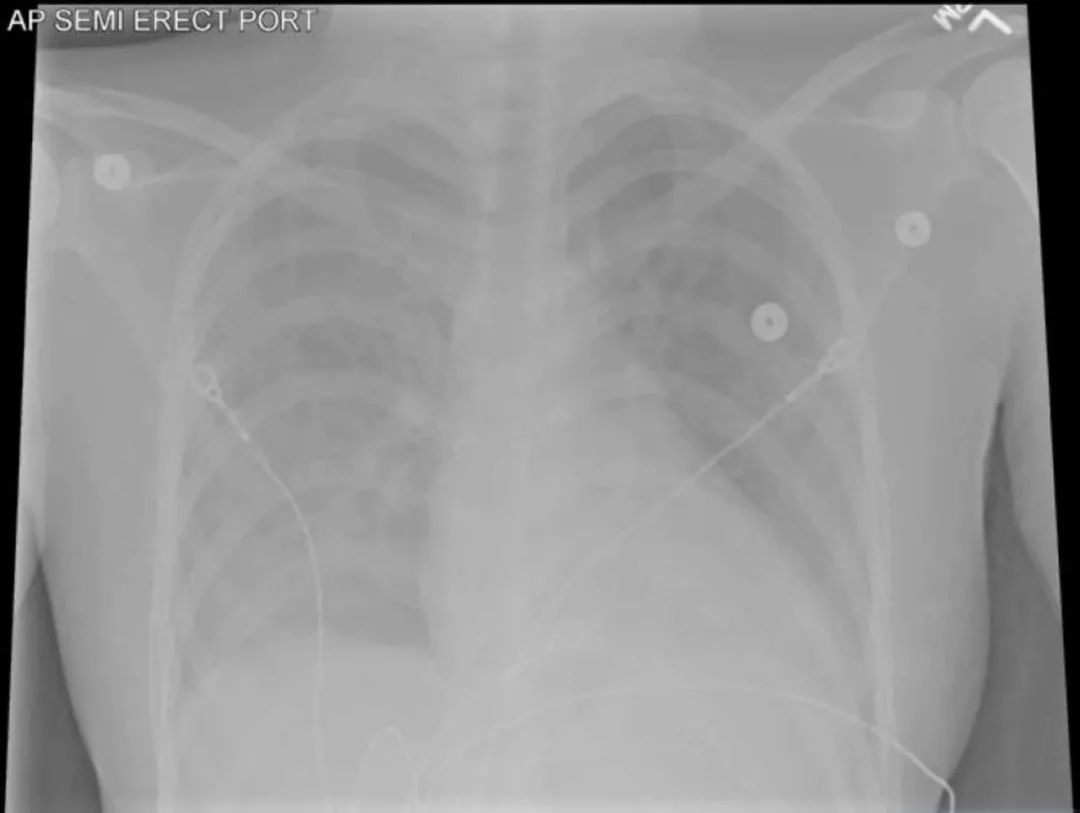

便携式胸片显示右肺弥漫性毛玻璃样阴影(图3)。